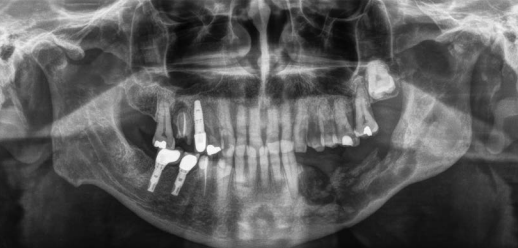

La osteonecrosis de los maxilares es una complicación poco frecuente pero importante. Se produce cuando una zona del hueso mandibular o maxilar no cicatriza correctamente y queda expuesta al medio oral durante más de ocho semanas, lo que puede causar infecciones, dolor y otras molestias.

Es un proceso en el cual una zona de la mandíbula o maxilar no consigue cicatrizar y se queda el hueso expuesto a la calidad oral, durante más de 8 semanas, causando infección y molestias